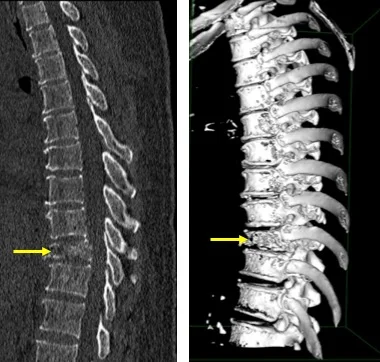

Diagnosis involves clinical evaluation, imaging tests like X-rays, MRIs, or CT scans, blood tests for inflammation markers (ESR, CRP), and tissue biopsy to confirm the presence of TB bacteria in the affected vertebrae.